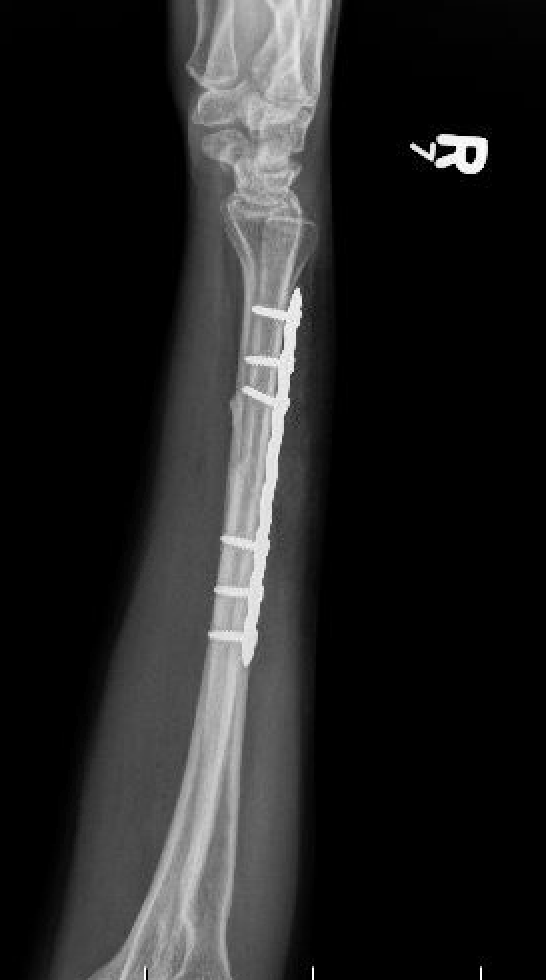

Compression plating

Ulna Intramedullary WireUlna Plating

Technique

AO foundation ulna plating

Ulna nonunion after plating